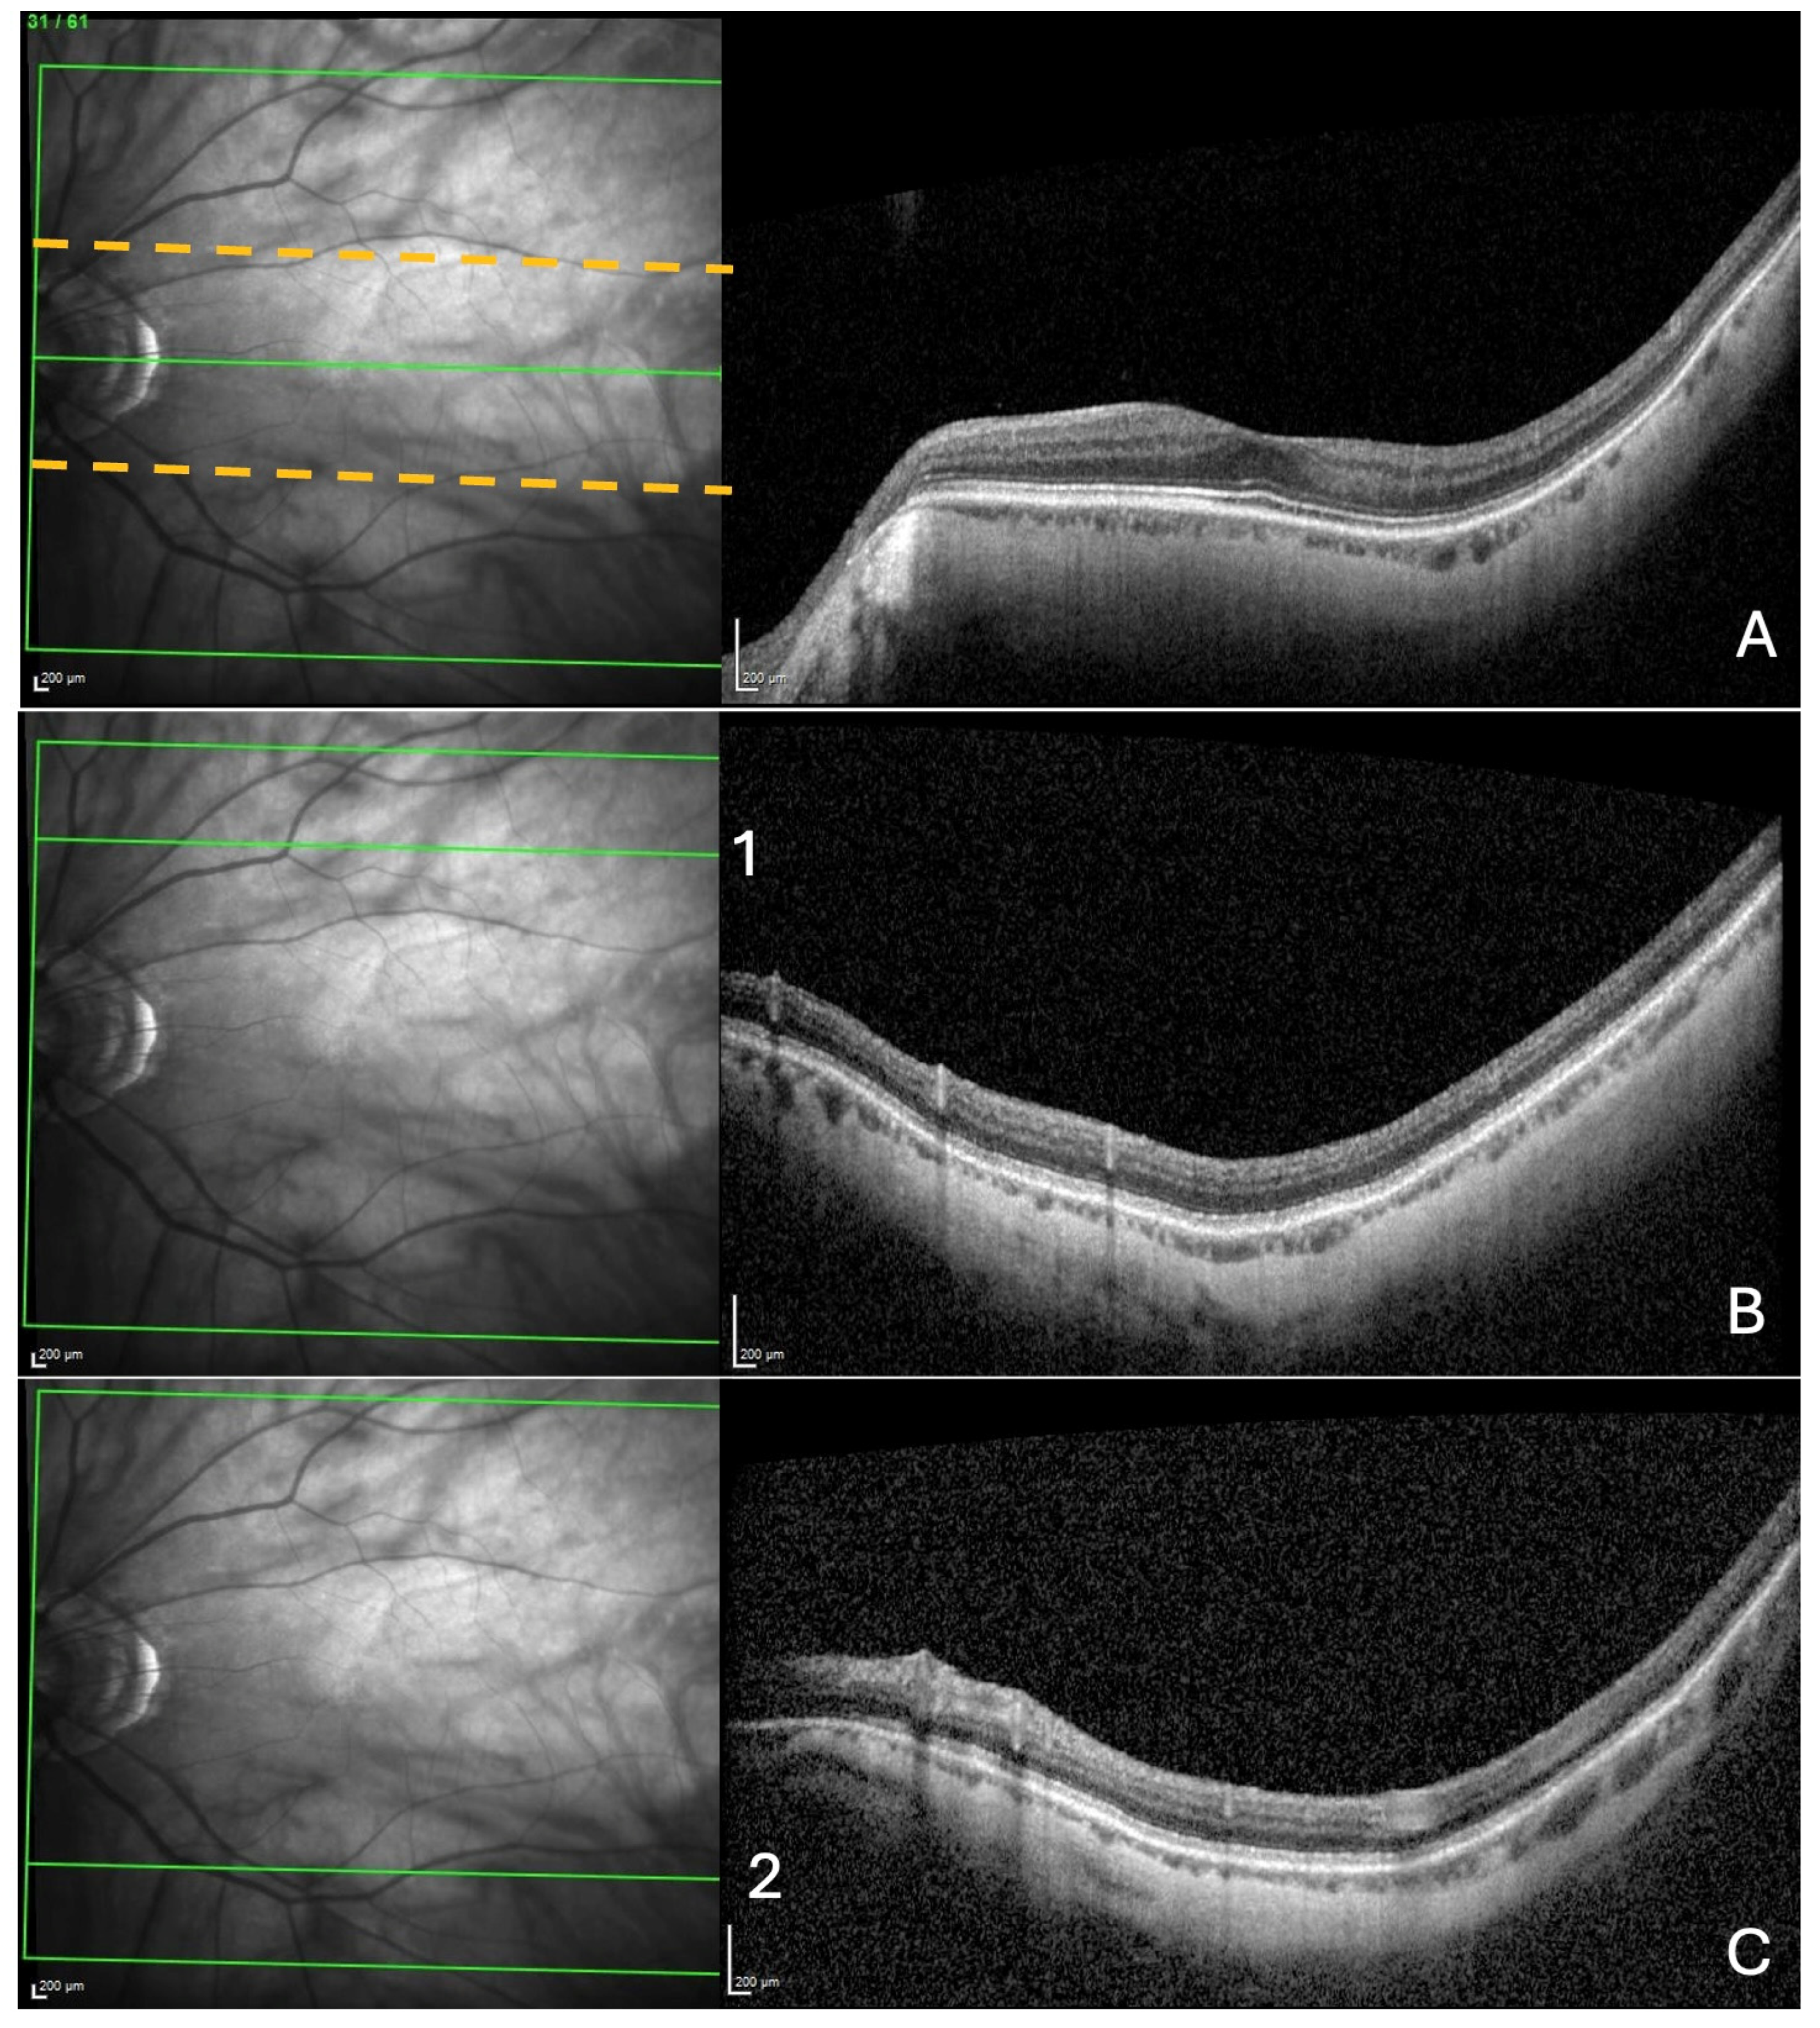

This was performed, respectively, near the fovea, and at the upper and lower limits of the acquisition rectangle. First, the rectangle acquisition band centered by the Bruch’s membrane opening–fovea (Fo-BMO) axis and including 10 sections below and 10 sections above this axis was assessed for the presence of a ChT (Figure 1A).

Figure 1.

Search for choroidal thinning in 3 locations. (A) In a band (delineated by the dashed yellow lines), including 10 cross-sections on either side of the fovea–Bruch’s membrane opening axis. (B) In the upper limit of acquisition rectangle (10 cross-sections) delineated by the green line (1) in the IR image. (C) In the inferior limit of acquisition rectangle (10 cross-sections) delineated by the green line (2) in the IR image.

Then, from the upper limit of the rectangle acquisition, ten outer sections were analyzed, looking for choroidal thinning in the same manner as described for the ChT (Figure 1B). Finally, the same procedure was performed in the lower limit of the acquisition rectangle (Figure 1C).